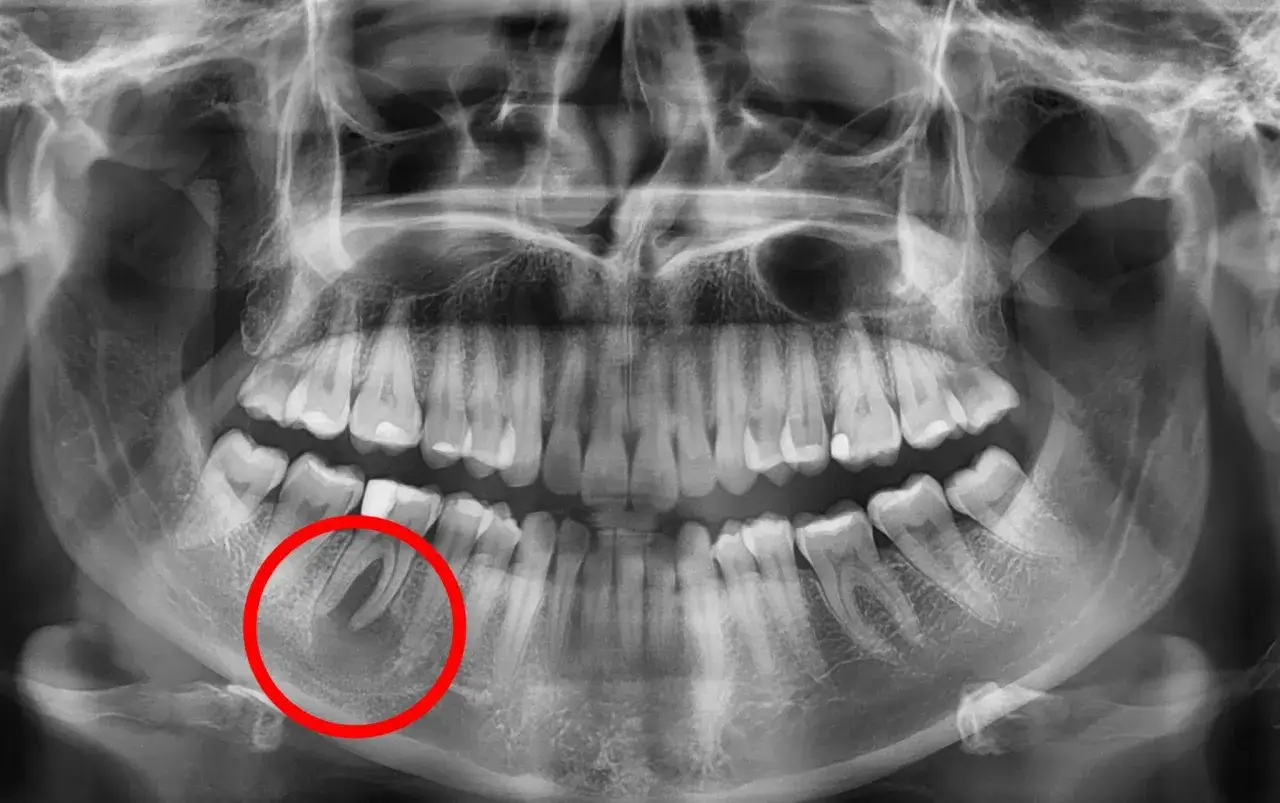

- Torbiel zęba często rozwija się bez bólu i bywa wykrywana przypadkowo na RTG.

- RTG jest zwykle pierwszym krokiem, a w trudniejszych przypadkach lekarz zleca CBCT, czyli tomografię stożkową.

W gabinecie nie wystarczy samo obejrzenie dziąsła. Lekarz zwykle zaczyna od wywiadu, badania jamy ustnej i testów zęba, a potem kieruje na obrazowanie. Najczęściej podstawą jest zdjęcie RTG, zwłaszcza pantomogram, bo pozwala zobaczyć związek zmiany z korzeniem, kością i sąsiednimi zębami. Gdy trzeba dokładniej ocenić zasięg, przydaje się CBCT, czyli tomografia stożkowa.

Ważne jest też to, że ostateczne rozpoznanie często potwierdza się dopiero po usunięciu zmiany, kiedy tkanka trafia do badania histopatologicznego. To standard, a nie nadmiar ostrożności. Dzięki temu lekarz wie, z jakim typem zmiany ma do czynienia i czy potrzebna jest dalsza kontrola.